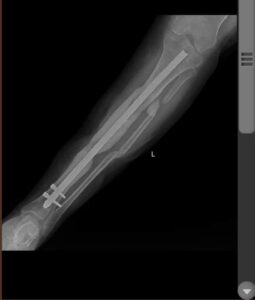

Bethany arrived at SCH with tibia and fibula fractures from a road traffic accident.

After 16 surgeries and 2 months in the hospital, she is now pain free and able to walk without a limp most days!